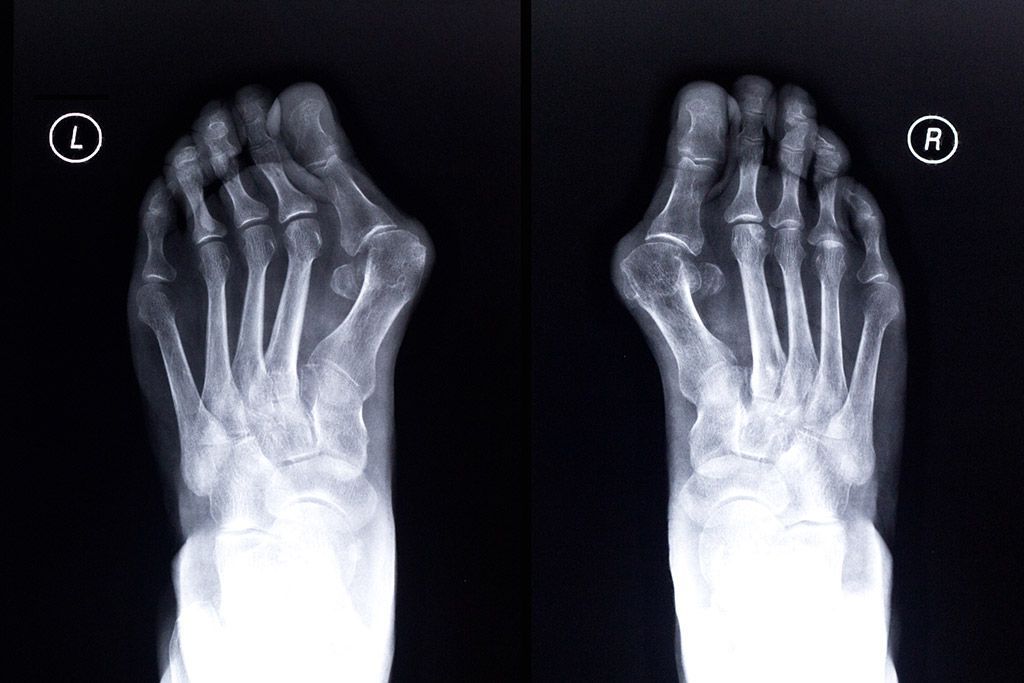

L'HALLUX VALGUS

L'hallux valgus communément appelé « l’oignon » est une déformation progressive du gros orteil (hallux) vers l'extérieur (valgus). Cette déformation est liée au déplacement de 2 os : le premier métatarsien et la première phalange du gros orteil. L’hallux valgus n’est pas lié à une production d’os sur le bord interne du pied. Il s’agit en fait de la tête du premier métatarsien qui fait sailli sur le bord interne du pied. Le gros orteil vient alors s’appuyer sur les orteils latéraux.

Quelles Radiographies dois-je faire avant de venir en consultation ?

Un simple bilan radiologique des 2 pieds face et profil en charge est nécessaire. Aucun autre examen radiologique ne doit être engagé à priori. Le bilan radiologique doit comporter des radiographies des deux pieds en charge de face et profil + des clichés des deux chevilles de face en charge avec fil de Méary.